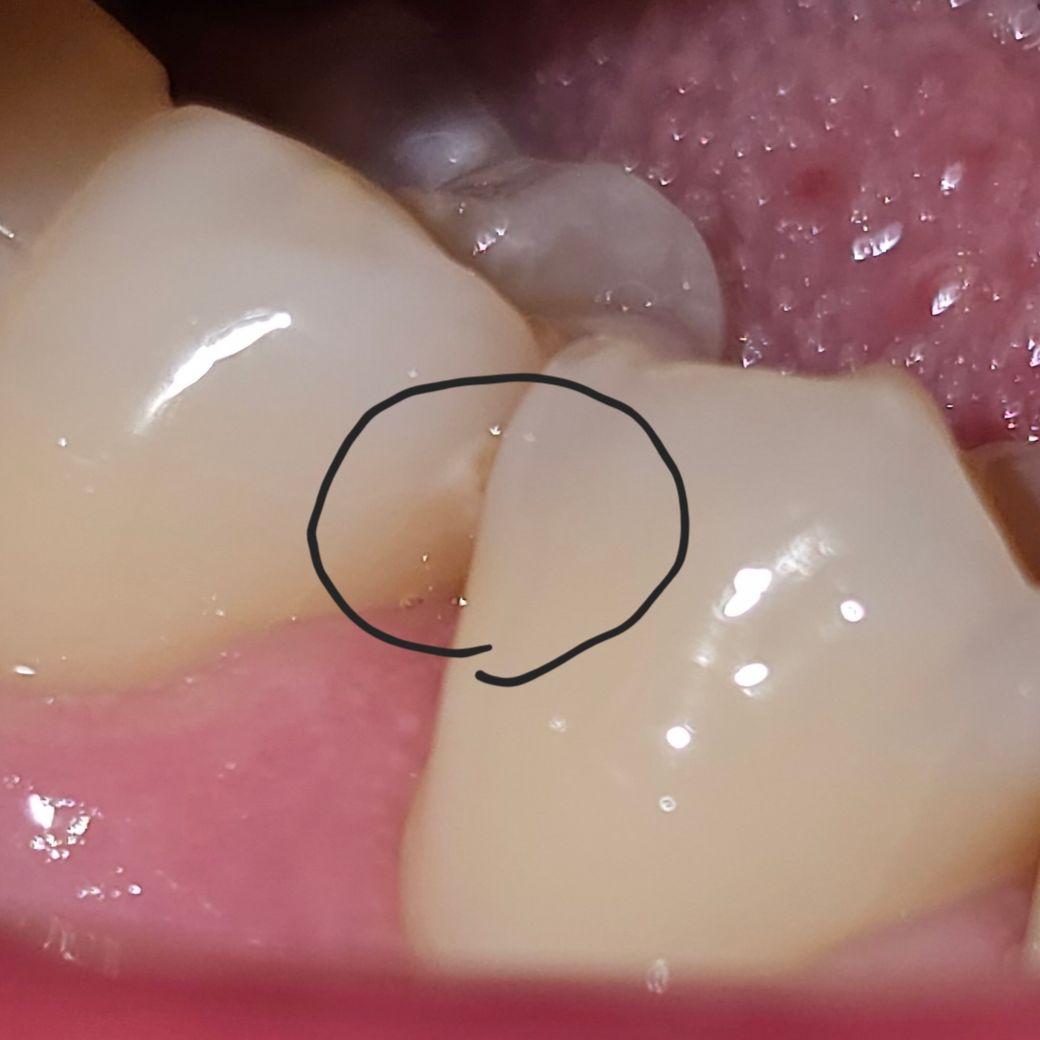

이 충치 인접면 충치 맞는건가요???

며칠 전 충치 치료 후 의사선생님이 이제 충치 없다고 하셨습니다. 그런데 집에서 스스로 확인 중 발견했는데 이거 인접면 충치 아닌가요? 선생님이 놓칠 수도 있나요?

인접면 충치가 맞습니다.

인접면 충치는 사진상으로 겹쳐서 찍히는 경우가 많고 육안상으로도 겹친 부분이 시야상 안 보이는 경우가 있습니다.

특히 사진상 인접면 충치는 아직 충치가 크지 않은 상태여서 이런 경우 놓치게 되는 경우가 종종 있습니다.

사진상으로 보면 충치의 양상으로 보이긴 합니다. 다만 보다 정확한 검사를 위해서는 해당부위 교익 방사선 사진을 찍어보면 좋을 것 같습니다. 교익 방사선 사진은 치아끼리 겹치지 않게 나와서 옆면 충치를 보다 잘 확인할 수 있습니다.